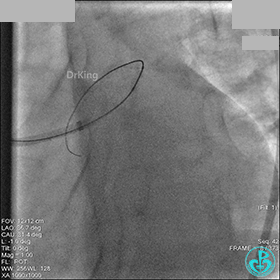

1周后再次上台,右冠脉3级血流,3段局限性严重狭窄,内膜模糊,应该是上次操作夹层遗留下的血肿。